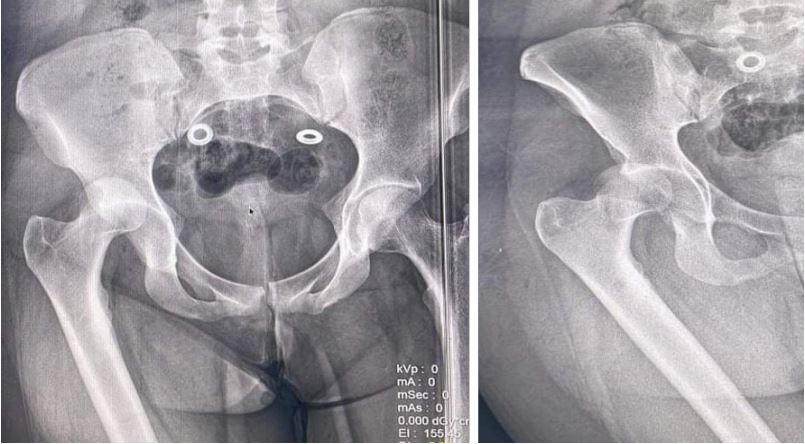

After successful release of the incarcerated muscles, the reduction was achieved easily (Figure 2).

Figure 2: Post-reduction X-rays.

The posterior-lateral approach provides excellent exposure of the posterior hip structures, but it carries the risk of injury to the medial circumflex artery [6,7]. In our case, the patient presented with irreducible hip dislocation due to incarceration of the lateral rotator group of hip muscles. The presence of the incarcerated muscles (Figure 2) and the subsequent sectioning of the posterior circumflex artery (Figure 3) were identified during the surgical procedure. It is important to consider irreducibility and the possibility of soft tissue incarceration in cases of failed closed reduction attempts.